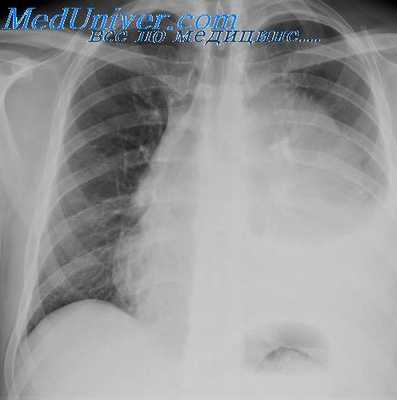

На рентгенограмме видна большая тень опухоли, с неровными контурами, занимающая переднее средостение, имеющая срединное положение. Определяется передаточная пульсация опухоли. Диагноз: лимфосаркома. 1/XI при пробной торакотомии установлено, что опухоль неоперабильна. Рентгенотерапия привела к быстрому уменьшению опухоли, но через 7 месяцев больной умер от множественных метастазов.